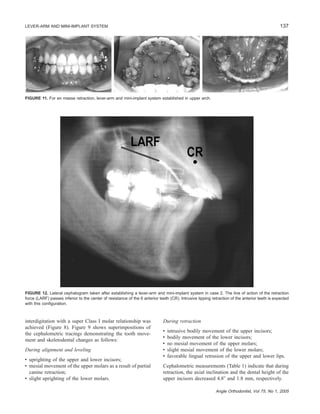

FIGURE 11. For en masse retraction, lever-arm and mini-implant system established in upper arch.

FIGURE 12. Lateral cephalogram taken after establishing a lever-arm and mini-implant system in case 2. The line of action of the retraction

force (LARF) passes inferior to the center of resistance of the 6 anterior teeth (CR). Intrusive tipping retraction of the anterior teeth is expected

with this configuration.

A progress lateral cephalogram was exposed 18 months

into treatment to evaluate the anterior tooth movement dur-

ing retraction. This revealed that the inclination of the upper

incisors was protrusive (Table 2). Therefore, the lever-arm

and mini-implant system for the upper arch was designed

to achieve intrusive tipping retraction of the anterior teeth

without anchorage loss (Figures 11 and 12). The appliances